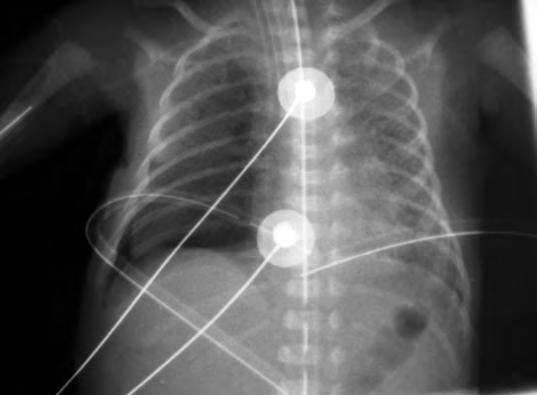

El examen microscópico muestra atelectasias generalizadas, ocupando las vías aéreas distales un material hialino compuesto de fibrina y residuos celulares epiteliales, debidos a necrosis celular, las “membranas hialinas”, que son la consecuencia y no la causa de la enfermedad. Además, el edema alveolar rico en proteínas inactiva el surfactante. El pulmón con déficit de surfactante precisa elevadas presiones para la apertura de los alvéolos colapsados, que son superiores a 25-30 cm H2O para los alvéolos de menor radio. Cuando el paciente es sometido a ventilación asistida, puede aparecer sobre-distensión y rotura de alvéolos de mayor diámetro, dando lugar a un enfisema intersticial y a un acúmulo de aire extrapulmonar (Fig. 2.18.2).

En un neonato pretérmino con dificultad respiratoria, el diagnóstico se basa en los antecedentes y, sobre todo, en el aspecto radiográfico de los pulmones, si bien la radiografía puede no reflejar la gravedad de la afectación pulmonar. La radiografía puede ser normal en los primeros momentos, pero progresivamente aparecen los cambios típicos, pero no patognomónicos de SDR: disminución del volumen pulmonar, opacificación difusa de los campos pulmonares con un moteado fino de aspecto de vidrio esmerilado y broncogramas aéreos. La imagen radiológica depende del ciclo respiratorio y del tipo de asistencia respiratoria recibida. Además, se debe valorar siempre la posible presencia de complicaciones, como enfisema intersticial, neumotórax o evolución hacia una displasia broncopulmonar (DBP). Puede aparecer cardiomegalia y aumento del flujo pulmonar por cortocircuito izquierda-derecha a nivel del ductus arterioso. La valoración de la expansión pulmonar es útil para ajustar los parámetros del ventilador.